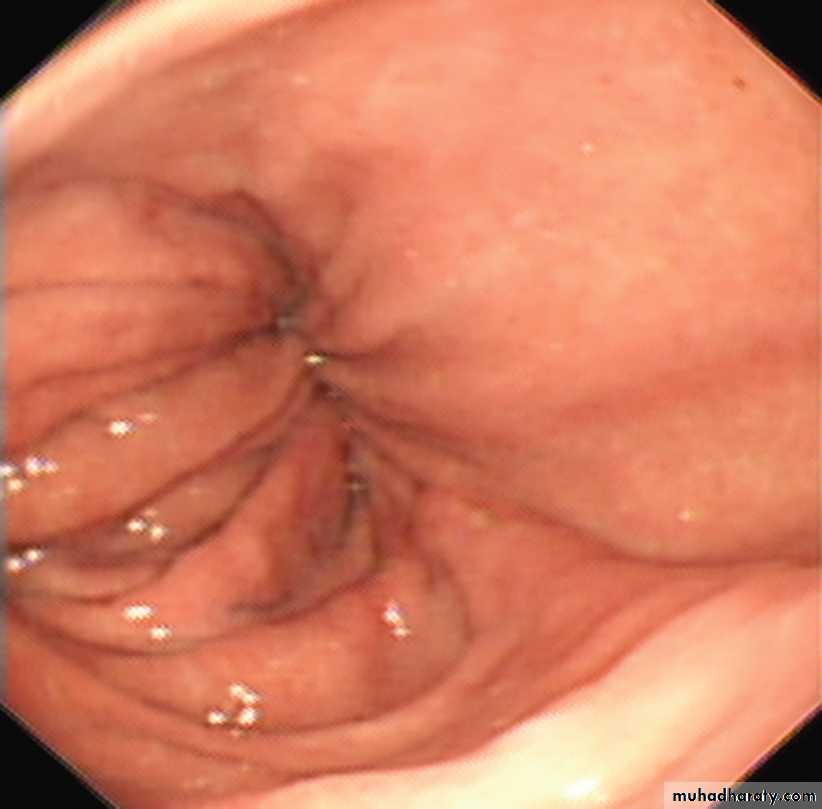

Endoscopy: must always be carried out, carcinoma of the cardia can mimic the presentation and radiological and manometric features of achalasia ('pseudo-achalasia').

Endoscopic view of hiatus hernia. A sliding hiatus hernia viewed from above.